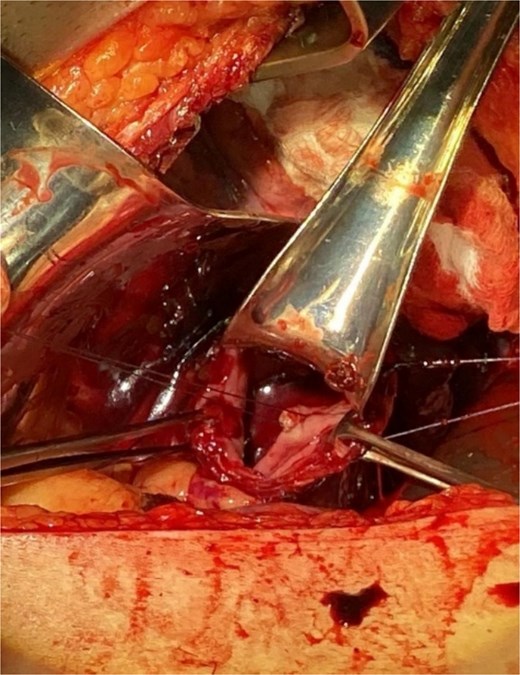

Surgical intervention was undertaken the day after admission. Both laparotomy and right anterolateral thoracotomy were performed. Intraoperative findings included markedly dilated and sigmoid-shaped esophagus, containing blood and residual food material. The initial surgical step involved mobilizing the esophagus from the hiatus, followed by a distal esophagotomy. Upon inspection, an active pulsatile arterial bleed was identified on the right lateral wall of the distal third of the esophagus, consistent with a Dieulafoy lesion. The bleeding vessel was successfully oversewn to achieve hemostasis (Fig. 3).

Illustrates the oversewing of the bleeding vessel to achieve hemostasis.